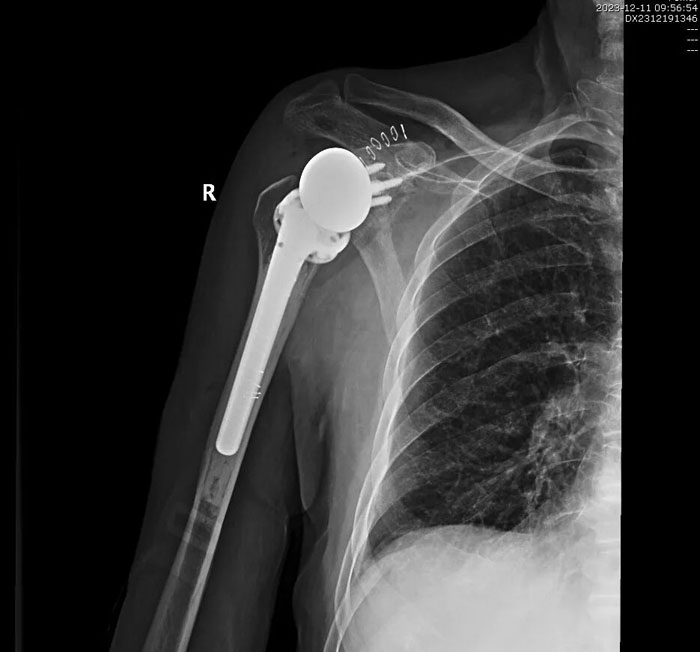

手術(shù)歷時(shí)2個(gè)小時(shí)順利完成,術(shù)后患者恢復(fù)良好,無(wú)并發(fā)癥發(fā)生,右肩關(guān)節(jié)功能明顯改善,患者對(duì)手術(shù)療效滿意。目前,患者已好轉(zhuǎn)出院,居家進(jìn)行功能康復(fù)鍛煉中。

術(shù)后